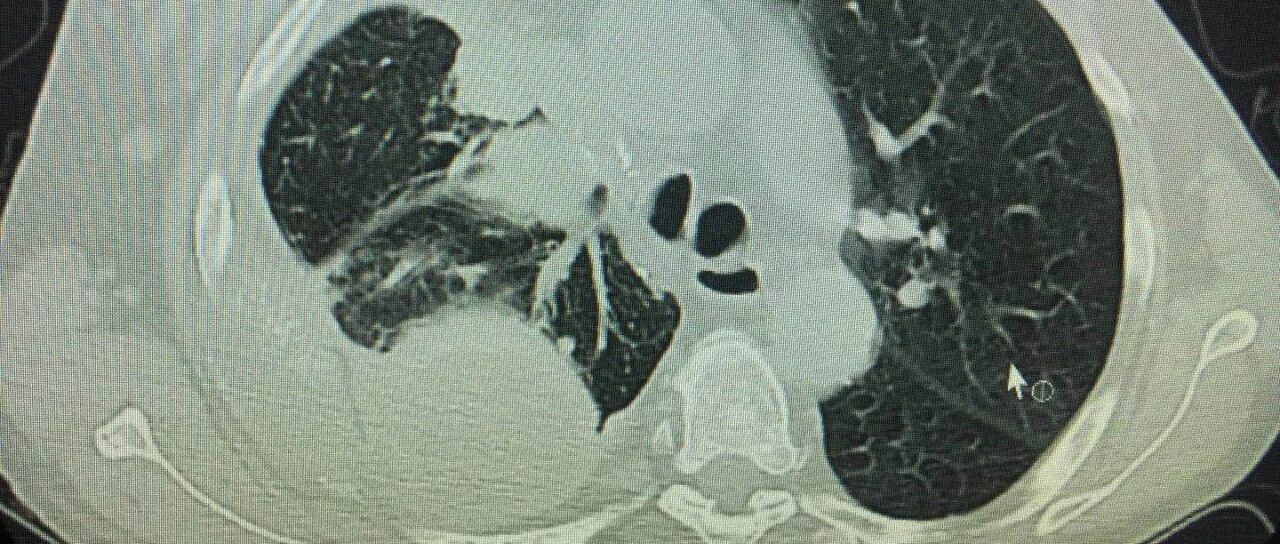

8月26日,医院又给陈阿姨做了CT,发现体内的癌细胞全部消失了。CAR-T细胞大获全胜,陈阿姨的癌症症状,也全部得到了缓解。